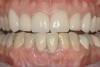

The final screw-retained crown was delivered and torqued onto the implant to 35 Ncm; the restorative dentist then sealed the screw access with a cotton pellet and composite (Figure 20 and Figure 21). Various views of the final crown are shown in Figure 22 through Figure 25, including a full-face photograph.

Figure 20  Screw-retained zirconia crown, customized zirconia stock abutment (one-piece restoration), site No. 9—final periapical view.

Figure 20

Figure 21  Screw access of final zirconia crown sealed with composite resin—incisal view.

Figure 21